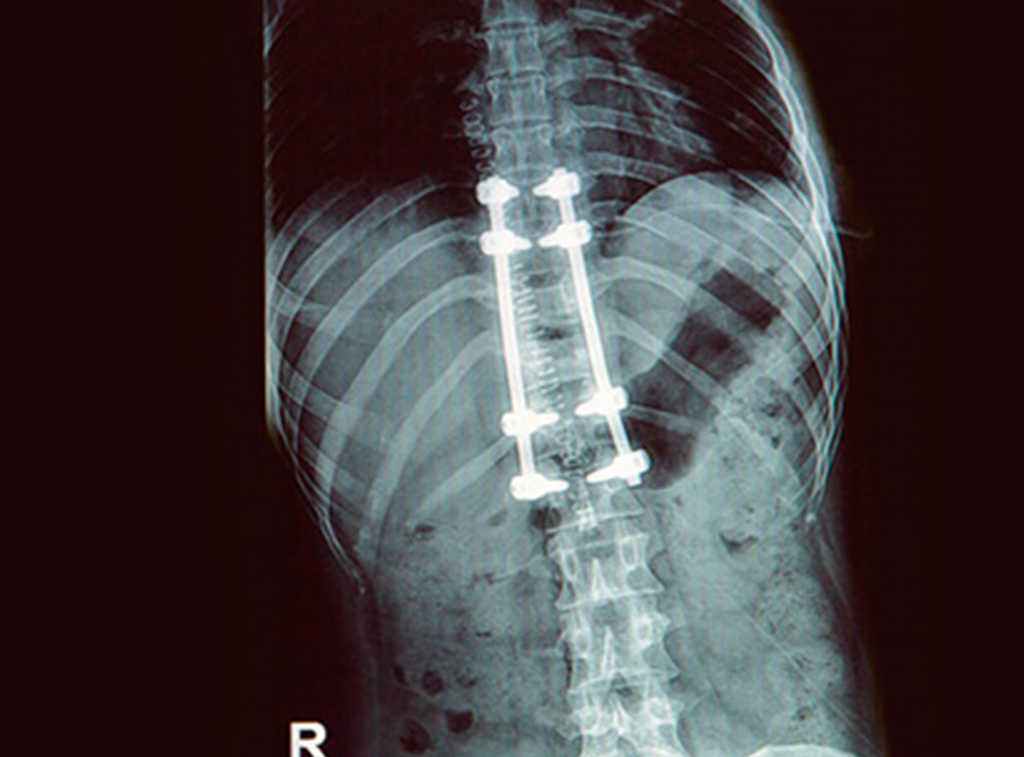

Cirugía

Cirugía Ortopédica y Traumatología

Prótesis ortopédicas

Implantes ortopédicos de columna

Cirugía de columna

Todos ellos pueden ser tratados con cirugía o, en algunos casos, con prótesis.